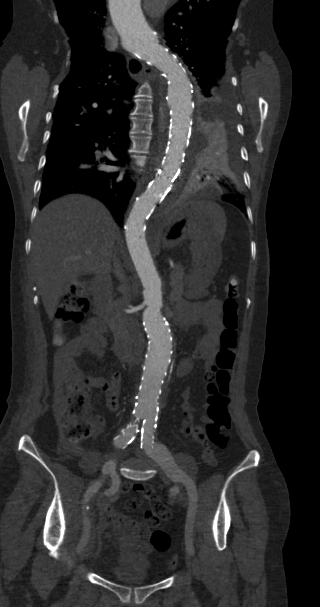

大范围低剂量CTA成像

采用业内最先进液态金属轴承技术的超大热容量球管,结合独有的低千伏、低毫安成像模式,天河640可实现冠脉、主动脉、下肢动脉等全身各部位大范围扫描、微辐射剂量的检查。低千伏扫描模式有效降低辐射剂量、对比剂总量、对比剂浓度、对比剂注射速率,降低肾功能不全受检者增强检查风险、减少对比剂外渗风险、并可大幅度提升增强检查碘对比剂对比度,提升强化效果;同时,系统还可根据不同患者体型和扫描协议自动推荐扫描管电压,在降低患者扫描剂量的同时,优化对比度噪声比。

联影ct怎么样科技助力健康丨“全球顶尖超高端”联影天河640层CT启用“满百天”_https://www.jmylbn.com_新闻资讯_第13张

联影ct怎么样科技助力健康丨“全球顶尖超高端”联影天河640层CT启用“满百天”_https://www.jmylbn.com_新闻资讯_第14张

图片说明:肺动脉+主动脉全程+下肢动脉大范围一次扫描成像。